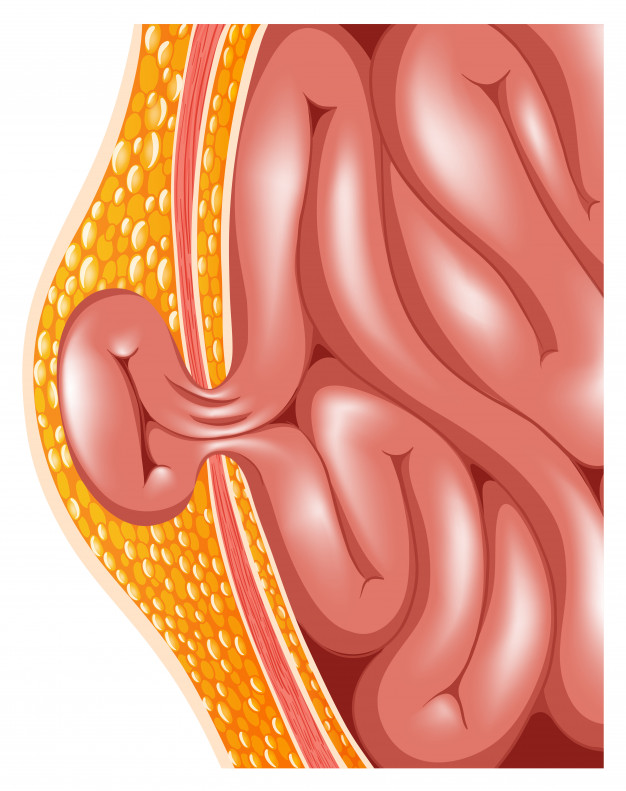

A hernia occurs when an internal organ pushes through a weak spot in the muscle wall, causing a visible bulge and discomfort.

A visible or noticeable bulge in the abdomen or groin often indicates a hernia and should be examined by a surgeon to avoid pain, complications, or enlargement.